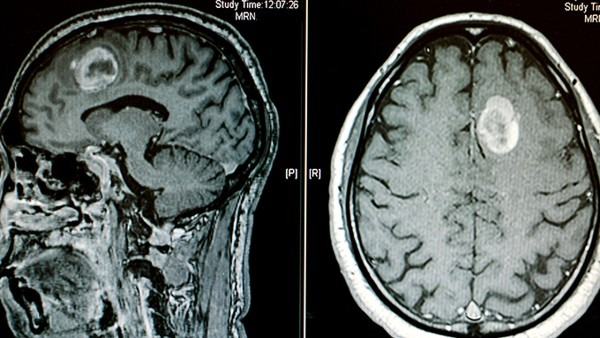

听神经瘤表现出的症状

首先,听神经瘤患者常常会出现渐进性单侧听力减退。这是因为神经瘤生长压迫了听神经,导致传递声音信号的功能受损。患者可能感觉到在一个耳朵听力明显减退,与另一只耳朵相比声音听起来较远或变得模糊不清。一开始,这听似无关紧要,但随着时间的推移,症状可能会逐渐加重。

除了听力减退和耳鸣,听神经瘤还可引起头痛和眩晕。这是因为神经瘤的生长可能会对周围组织和神经产生压力。这种压力可能会触发头痛,有时甚至发展成为持续的偏头痛。眩晕是另一种常见的症状,患者可能感觉头晕目眩,失去平衡和出现轻微的晕倒感。

另外,听神经瘤可能会对面部神经造成影响,导致一侧面部肌肉松弛或麻木。这可能表现为面部表情不对称,例如口角歪斜或眼睑下垂。患者还可能有困难控制面部肌肉,例如闭眼或露齿微笑。

总体而言,听神经瘤的症状是多样的,因人而异。如果出现单侧听力减退、耳鸣、头痛、眩晕或面部肌肉异常等症状,建议及时就医检查。早期诊断和治疗可以帮助减轻症状,提高生活质量。虽然神经瘤可能需要外科手术或其他治疗方法来处理,但通过专业医生的帮助和关注,患者有望获得更好的康复效果,重拾健康和幸福的生活。